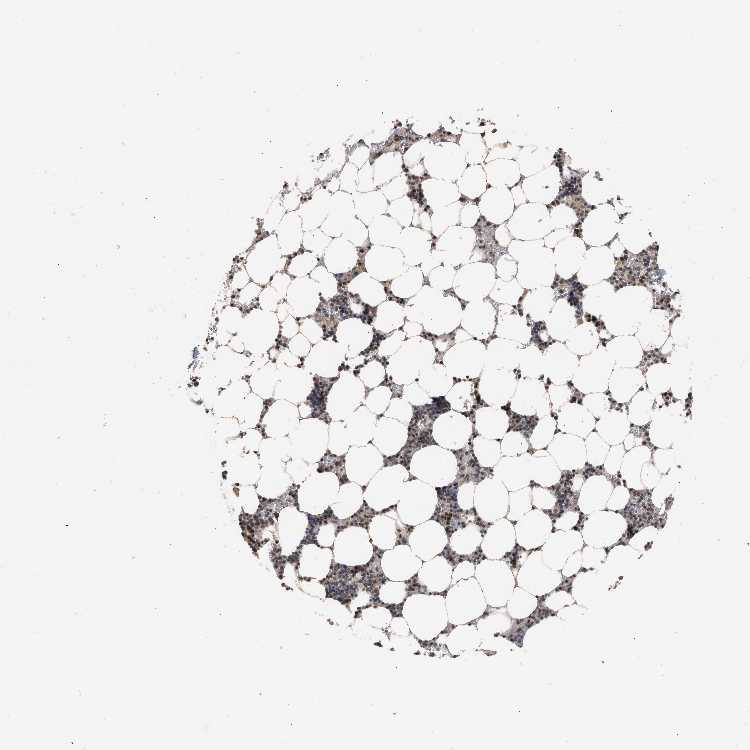

BONE MARROW - Antibody stainingi

Antibody staining in the annotated cell types in the current human tissue is reported as not detected, low, medium, or high, based on conventional immunohistochemistry profiling in selected tissues. This score is based on the combination of the staining intensity and fraction of stained cells.

Each image is clickable and will lead to virtual microscopy that enables deeper exploration of all samples and also displays staining intensity scores, fraction scores and subcellular localization as well as patient and tissue information for each sample.

Antibody CAB019271

Hematopoietic cells Low